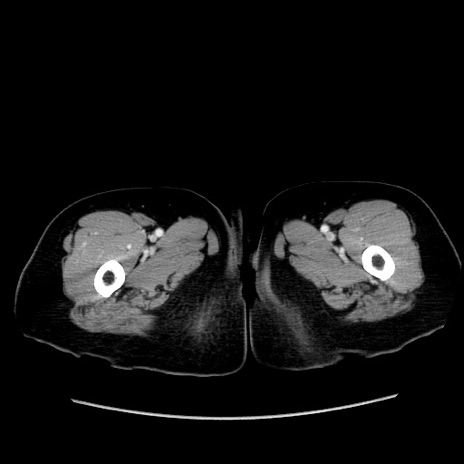

冠状断像

【症例】80歳代女性

【主訴】下腹部痛

【現病歴】約8時間前より下腹部痛の出現あり、救急外来受診。

【既往歴】両側付属器切除

【身体所見】意識清明、下腹部正中に手術痕あり、その部位に一致して圧痛と反跳痛あり。腸蠕動音は亢進。

【データ】WBC 9300、CRP 0.15